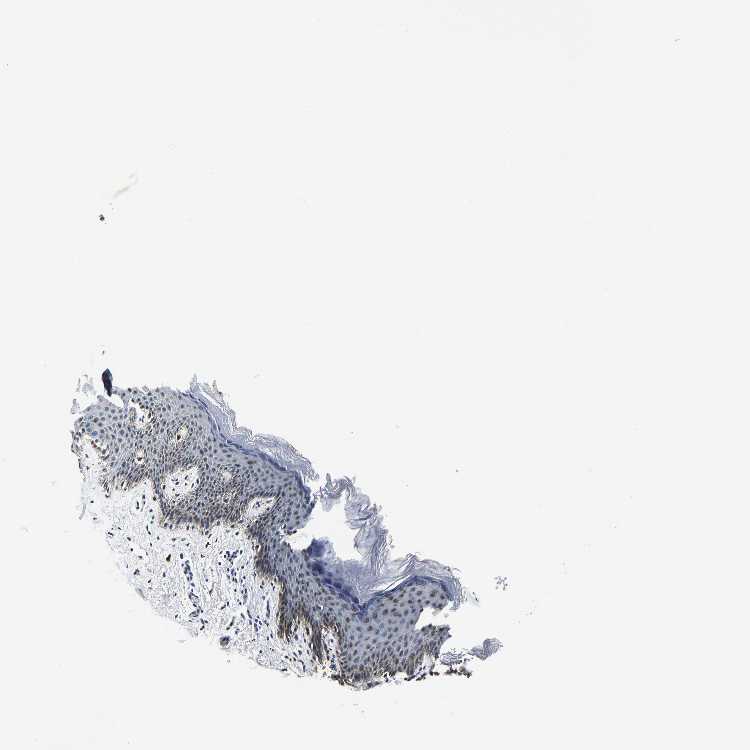

SKIN 2 - Antibody stainingi

Antibody staining in the annotated cell types in the current human tissue is reported as not detected, low, medium, or high, based on conventional immunohistochemistry profiling in selected tissues. This score is based on the combination of the staining intensity and fraction of stained cells.

Each image is clickable and will lead to virtual microscopy that enables deeper exploration of all samples and also displays staining intensity scores, fraction scores and subcellular localization as well as patient and tissue information for each sample.

Antibody HPA020448

Epidermal cells Low